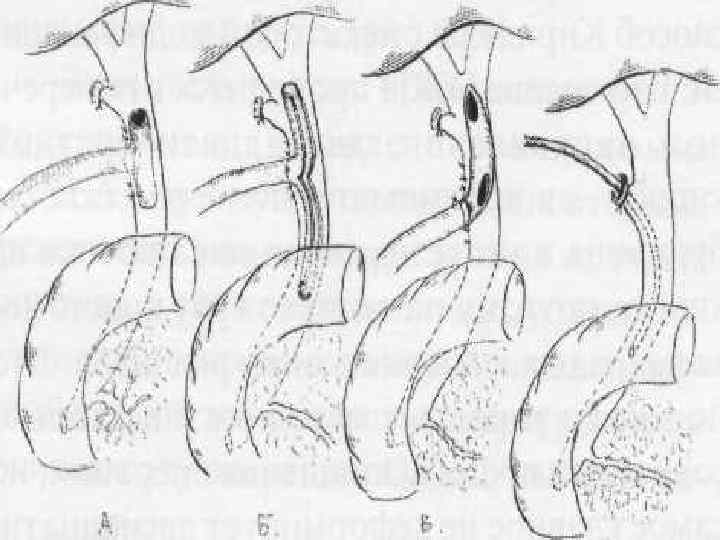

Варианты соединения общего желчного протока с протоком поджелудочной железы

Варианты соединения общего желчного протока с протоком поджелудочной железы